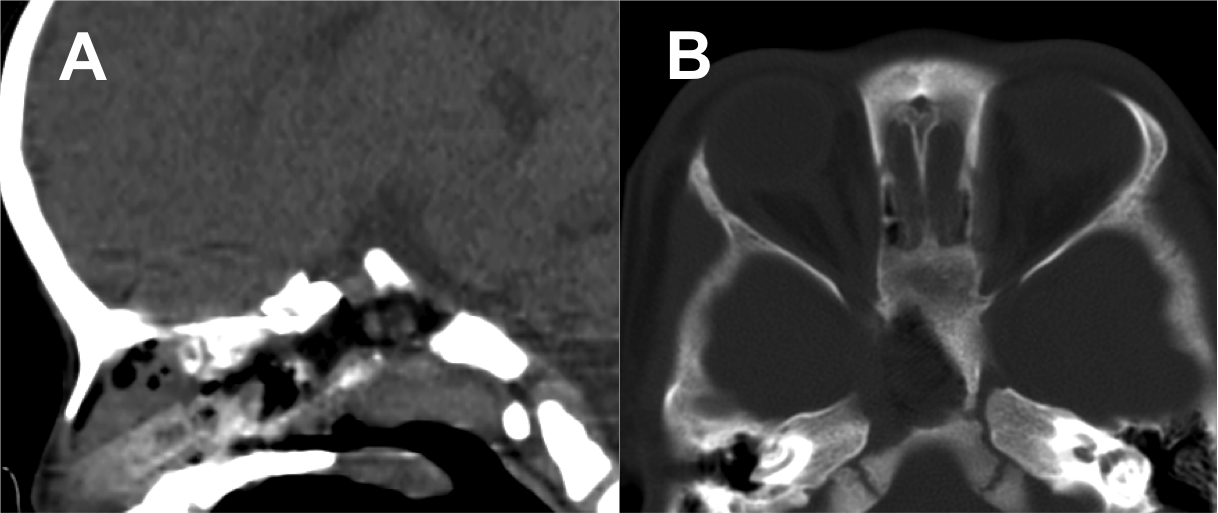

Introducción: La cirugía endoscópica endonasal se ha convertido en una herramienta fundamental para el manejo de patologías que comprometen la base de cráneo. En casos bien seleccionados, estas técnicas permiten resecciones quirúrgicas con una menor morbilidad sin comprometer los principios oncológicos de resección. Con el desarrollo de instrumental especializado, nuevas tecnologías y la experiencia de los cirujanos, la cirugía endoscópica endonasal se usa cada vez más en cirugía de base de cráneo en niños.

Resultados: Fueron intervenidos 8 pacientes entre los 2 y 14 años, con una edad promedio de nueve años y un seguimiento promedio de 16 meses. En el 75% se hizo una resección total del tumor. Un paciente requirió una reintervención y un paciente fue sometido a radiocirugía post-operatoria. 1 paciente falleció a pesar de múltiples intervenciones, quimioterapia y radioterapia.

Conclusión: La cirugía endoscópica endonasal para tumores de base de cráneo puede ser utilizada de forma segura en los pacientes pediátricos, es una técnica que en casos bien seleccionados pueden ofrecer excelentes resultados disminuyendo la morbilidad y complicaciones de las técnicas abiertas.